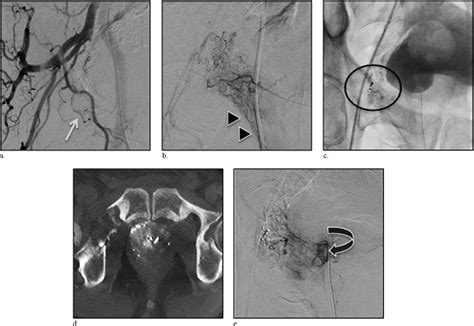

The Prostate Embolization Technique is typically performed under local anesthesia with sedation. The steps involved are as follows:

1. Accessing the Blood Vessels: The interventional radiologist makes a small incision in the groin area and inserts a thin catheter into the femoral artery.

2. Guiding the Catheter: Using imaging guidance, the catheter is carefully navigated to the arteries supplying the prostate.

3. Embolization: Small particles are injected through the catheter into the prostate arteries, blocking blood flow and causing the prostate to shrink.

4. Completion: Once the embolization is complete, the catheter is removed, and the incision is closed with a small bandage.